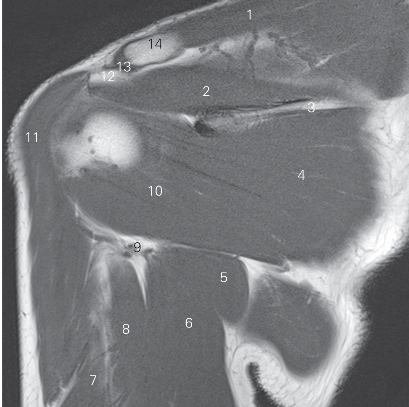

图4-22 经肩关节盂的矢状断层MR T2WI FS

1 锁骨 clavicle 2 冈上肌 supraspinatus

3 肩胛冈 spine of scapula 4 冈下肌 infraspinatus

5 小圆肌 teres minor 6 三角肌 deltoid

7 肱三头肌长头 long head of triceps brachii

8 大圆肌 teres major

9 腋窝血管神经束 axillary neurovascular bundle

10 关节盂 glenoid cavity 11 胸小肌 pectoralis minor

12 胸大肌 pectoralis major

13 喙突下滑囊 bursa mucosa of inferior coracoid pocess

14 喙突 coracoid prcess